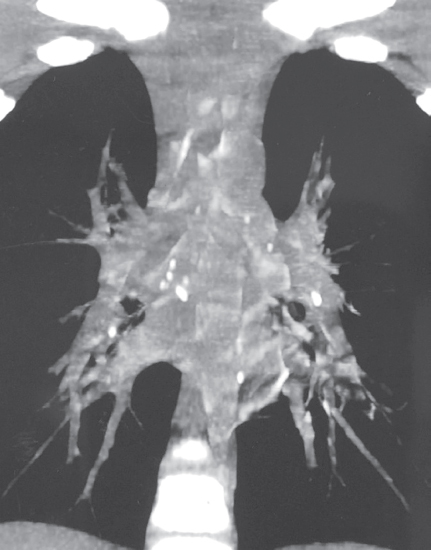

According to scientific research, malignant neoplasms in children are biomedical risk factors for the development of tuberculosis (TB). On the contrary, the occurrence of oncological disease in a child against the background of an existing tuberculous process is extremely rare. The combination of malignant neoplasm and tuberculosis creates difficulties in differential diagnosis, treatment of diseases, prevention of exacerbations and relapses. This article presents a clinical observation – the development of acute lymphoblastic leukemia (ALL) in a 6-year-old child against the background of TB of the intrathoracic lymph nodes during treatment. TB proceeded favorably despite multiple family contact in the child and resistance of Mycobacterium tuberculosis to anti-tuberculosis drugs in adult relatives of the patient. At the onset of ALL, bilateral pulmonary infiltrates and pleural effusion were observed, which were not associated with TB. Specific polychemotherapy for ALL and continued chemotherapy for TB led to the cure of two diseases. Supportive cytostatic and immunosuppressive therapy for ALL required periodic courses of anti-relapse anti-tuberculosis therapy for 5 years. After 10 years of observation, the child is healthy. Thus, the possibility of a rare in clinical practice combination of TB and ALL in children should be taken into account in the diagnosis and treatment of these diseases. During courses of immunosuppressive therapy for ALL, there is a risk of reactivation of TB. It is necessary to recommend long-term observation of such children by a phthisiatrician and an oncologist to prevent recurrence of both diseases.